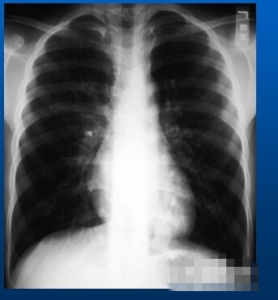

本病早期體徵多無異常,嚴重肺氣腫者胸廓前後徑增加,外觀呈桶狀,肋間隙飽滿。叩診胸廓迴響增加,心濁音界縮小或消失,肝濁音界下降。呼吸音和語音均減弱,呼氣延長,有時兩肺底可聞及乾濕囉音。心音低遠。本病由於肺臟過度充氣,殘氣量增加,X線檢查肺透明度增加,但在早期這一X線徵象不夠敏感。重度肺氣腫時胸廓飽滿,肋骨走行變平,肋間隙增寬。側位片胸廓前後徑增大,胸骨後間隙過寬。膈肌位置下移,膈穹隆變為扁平。兩肺透明度增高,肺野外帶血管紋理纖細、稀疏。心影呈垂直狹長。透視下可見胸廓和膈肌活動度減弱。也有表現為肺紋理增多的,肺透明度增高不明顯,肺門部肺動脈增寬,心臟常擴大。

3.X線檢查

胸廓擴張飽滿,肺容積增大,肋間隙增寬,肋骨平舉。側位胸片見胸廓前後徑增寬,心前間隙增大。橫膈低位,膈穹隆變平。肺野透光度增大,有時可見局限性透光度增高的局限性肺氣腫或肺大皰。肺野外帶肺血管紋理纖細、稀疏、變直;而內帶紋理可增粗、紊亂。心臟常呈垂直位,心影狹長。透視下可見胸廓和膈肌活動度減弱。